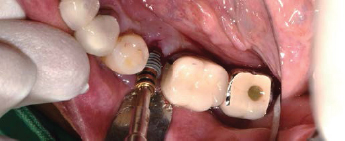

Volume Up Gauge홈에 맞춰 Point Drill 위치

Point Drill 후 생성된 구멍에 Ø8.5 Volume Up Parallel Pin을 끼움

이 후, 앞의 임플란트 위치에 맞춰 Volume Up Gauge 위치 시켜 직경확인 (Ø7.5)

Volume Up Gauge 홈에 맞춰 Point Drill 위치

Point Drill 후 생성된 구멍에 Ø7.5 Volume Up Parallel Pin을 끼움